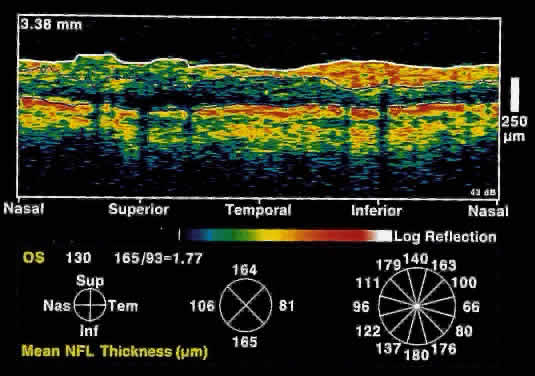

OCT, because of its high resolution, is able to detect nerve fiber layer thinning before the onset of visual changes.21 Nerve fiber layer thickness, as measured by OCT, has been shown to correspond to visual function. As expected from the histology of the peripapillary retina, the nerve fiber layer is thickest in the inferior and superior quadrants. The nerve fiber layer has been demonstrated to be significantly thinned in areas corresponding to visual field loss.

Typically, the scans are performed radially around the optic nerve for 360° using two radii of curvature (2.25 and 3.37 mm), and the nerve fiber layer thickness is plotted schematically (Fig. 16). Normal nerve fiber layer thickness is a mean of 148.6 microns for superior nerve fibers, 143.5 microns for inferior nerve fibers, 66.9 microns for temporal nerve fibers, and 117.2 for nasal nerve fibers. The direct measurement of the nerve fiber layer thickness by OCT is an objective assessment of glaucomatous progression. OCT shows promise in the early diagnosis of glaucoma before visual field defects, optic nerve head changes, and ophthalmoscopically visible nerve fiber layer loss are evident.

Fig. 16. Circular OCT image of a normal eye taken in cylindrical section around the optic nerve head. Note the thicker nerve fiber layer superiorly and inferiorly.